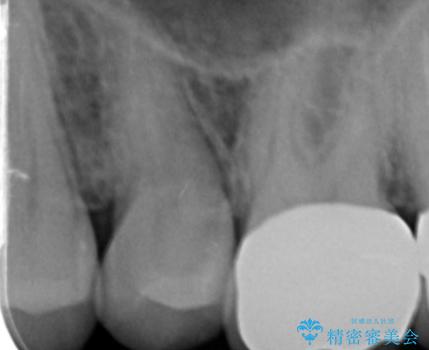

銀の詰め物を拡大鏡下で取り除き、う蝕がないことを確認してから

ZrCrの被せ物で治療を行いました。

また、一つ手前の歯に小さな虫歯があったため

e-maxインレーでの治療を行いました。

銀の詰め物の範囲が大きいほど

やりかえをする時、セラミックの詰め物だと割れるリスクがあるため

ZrCrの被せ物のご案内をする事があります。